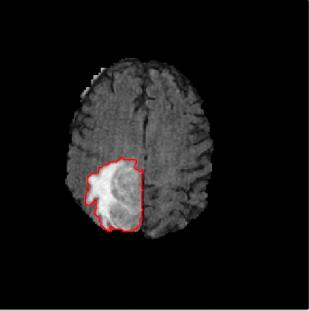

Machine learning has been widely adopted for medical image analysis in recent years given its promising performance in image segmentation and classification tasks. The success of machine learning, in particular supervised learning, depends on the availability of manually annotated datasets. For medical imaging applications, such annotated datasets are not easy to acquire, it takes a substantial amount of time and resource to curate an annotated medical image set. In this paper, we propose an efficient annotation framework for brain MR images that can suggest informative sample images for human experts to annotate. We evaluate the framework on two different brain image analysis tasks, namely brain tumour segmentation and whole brain segmentation. Experiments show that for brain tumour segmentation task on the BraTS 2019 dataset, training a segmentation model with only 7% suggestively annotated image samples can achieve a performance comparable to that of training on the full dataset. For whole brain segmentation on the MALC dataset, training with 42% suggestively annotated image samples can achieve a comparable performance to training on the full dataset. The proposed framework demonstrates a promising way to save manual annotation cost and improve data efficiency in medical imaging applications.

翻译:近年来,由于在图像分割和分类任务方面表现良好,医学图像分析广泛采用了机器学习。机器学习的成功,特别是监督学习的成功,取决于手动附加说明数据集的可用性。对于医疗成像应用来说,这种附加说明数据集不容易获得,需要大量的时间和资源来翻译附加说明的医学成像集。在本文件中,我们建议为大脑MR图像建立一个高效的注释框架,为人类专家提供信息性样图像,供人类专家作说明。我们评估了两种不同的大脑图像分析任务的框架,即脑肿瘤分割和整个大脑分割。实验显示,对于BRATS 2019数据集的脑肿瘤分割任务,培训一个只有7%的附加说明图像样本的分解模型,其性能与全数据集培训的性能相当。对于MALC数据集的整个大脑分割,用42%的附加说明性图像样本进行的培训,可以实现与全数据集培训的类似性能。拟议的框架展示了节省人工注解成本和提高医疗成像应用数据效率的有希望的方法。